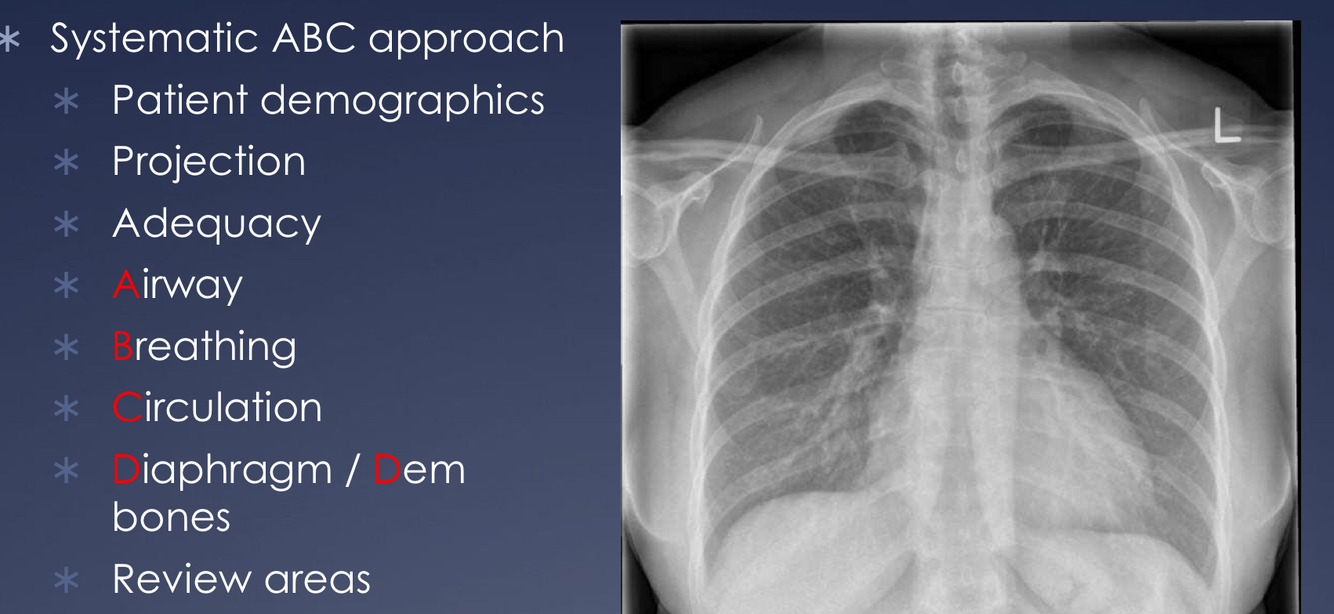

How do you systematically review a chest x-ray?